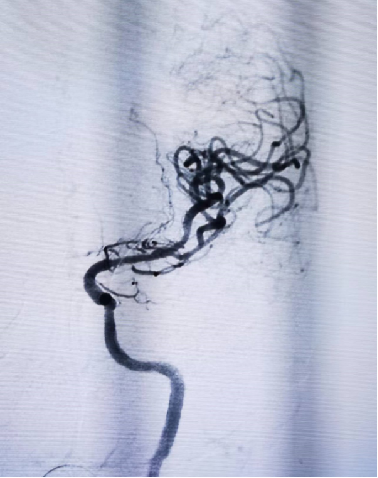

导丝怎么扩【载药时代 球扩天下】NOVA DES®颅内药物洗脱支架在大脑中动脉重度狭窄中的应用两例!_https://www.jmylbn.com_新闻资讯_第7张

导丝怎么扩【载药时代 球扩天下】NOVA DES®颅内药物洗脱支架在大脑中动脉重度狭窄中的应用两例!_https://www.jmylbn.com_新闻资讯_第8张

颈动脉支架释放

在微导丝辅助下将2.25*10mm赛诺神畅颅内药物洗脱支架NOVA DES®于大脑中动脉狭窄处扩张成形术。